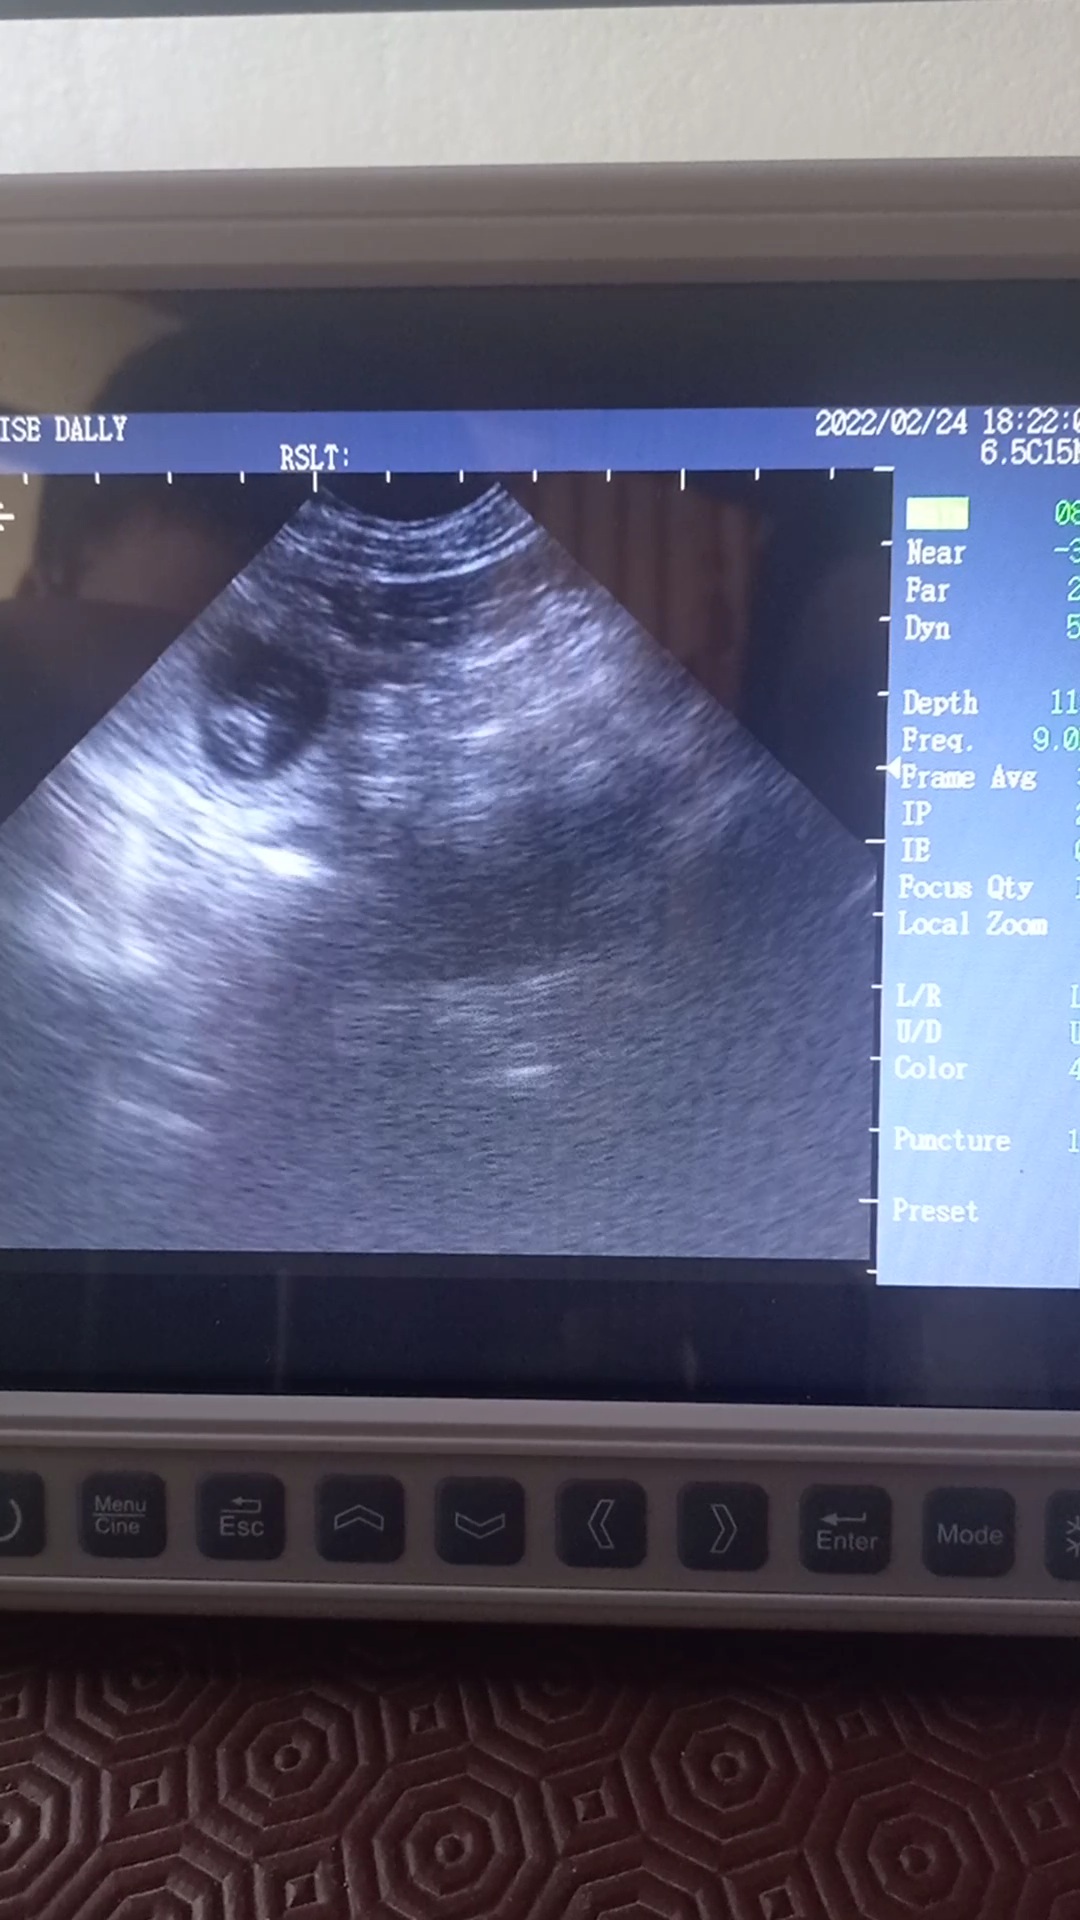

Beautiful scan of a 4yr old Labrador, confirmed multiple pups at 30days.